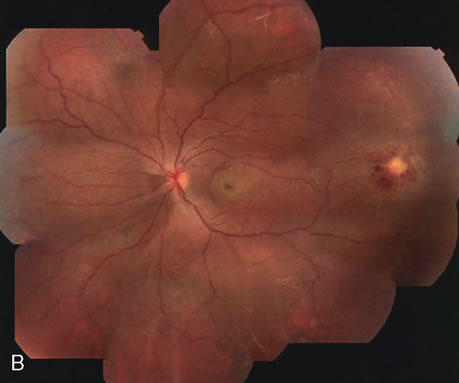

Fig. 16. Subfoveal, juxtafoveal, and extrafoveal choroidal neovascular membranes. A and B. Large subfoveal choroidal neovascularization (CNV) in a 69-year-old man with blood and pigment blocking central fluorescence on both the early-phase (A) and late-phase (B) photographs. The hypofluorescence surrounding the membrane is commonly seen in CNV and may be due to lipofuscin. C. Juxtafoveal CNV in a 37-year-old man with idiopathic CNVM. D. Cuticular drusen in same patient as in C were asymptomatic. E. Years later, this same patient developed a large extrafoveal CNV with central macular pigment abnormalities. A large neurosensory detachment was responsible for the disappearance of the drusen. (Courtesy of Dr. Kenneth G. Noble.)

Conventional laser thermophotocoagulation is the treatment of choice for extrafoveal, well-defined, classic CNV. Photodynamic treatment (PDT) is the treatment of choice for subfoveal, predominantly classic CNV. FA is used to localize the lesion in relation to the fovea, classify the subtype, choose the type of procedure, and guide the treatment (Figs. 18, 19, and 20).56–73